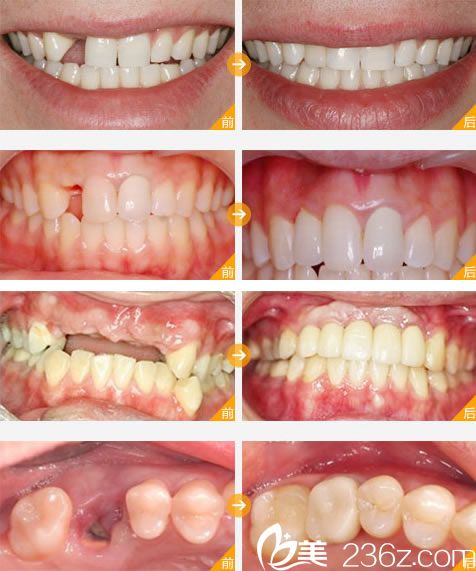

【宁波牙博士王道军院长微创即刻种植牙真人案例效果图片】

技术简介:微创即刻种植牙技术,是国外牙博士齿科集团20多年临床与科研的精华,以安全性、微创性、精准性、即刻性和高成功率在齿科种植修复界独树一帜。该技术依托口腔数字化工作平台,在具有丰富临床经验的医生操作下,通过全新3D全景CT扫描定位立体成像,计算出患者缺牙部位的牙骨组织情况,准确计算出种植牙的位置、角度、深度,做到量体裁衣一气呵成。

技术亮点:该技术针对牙槽骨情况好的患者可以即刻种植即刻修复,就是种完马上安装牙冠,不需要像传统种植牙埋入3个月后割开做二期修复(二期修复2个星期后拆线,拆完线再等一个星期才能带牙)。